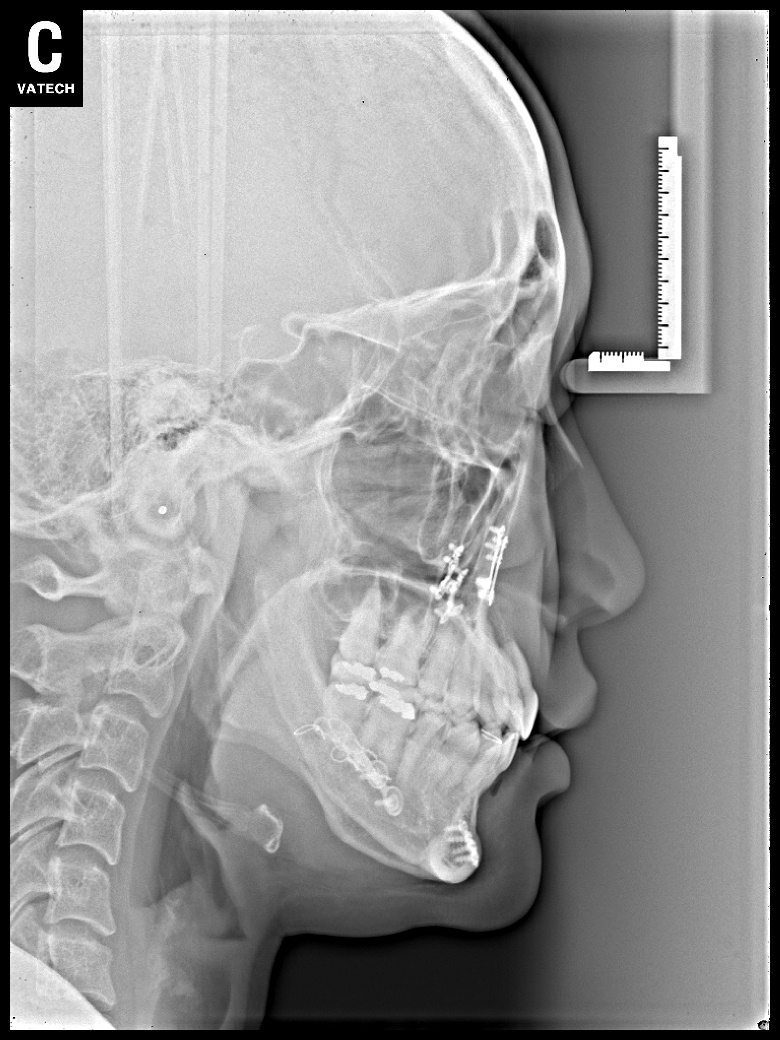

치료 전 사진입니다.